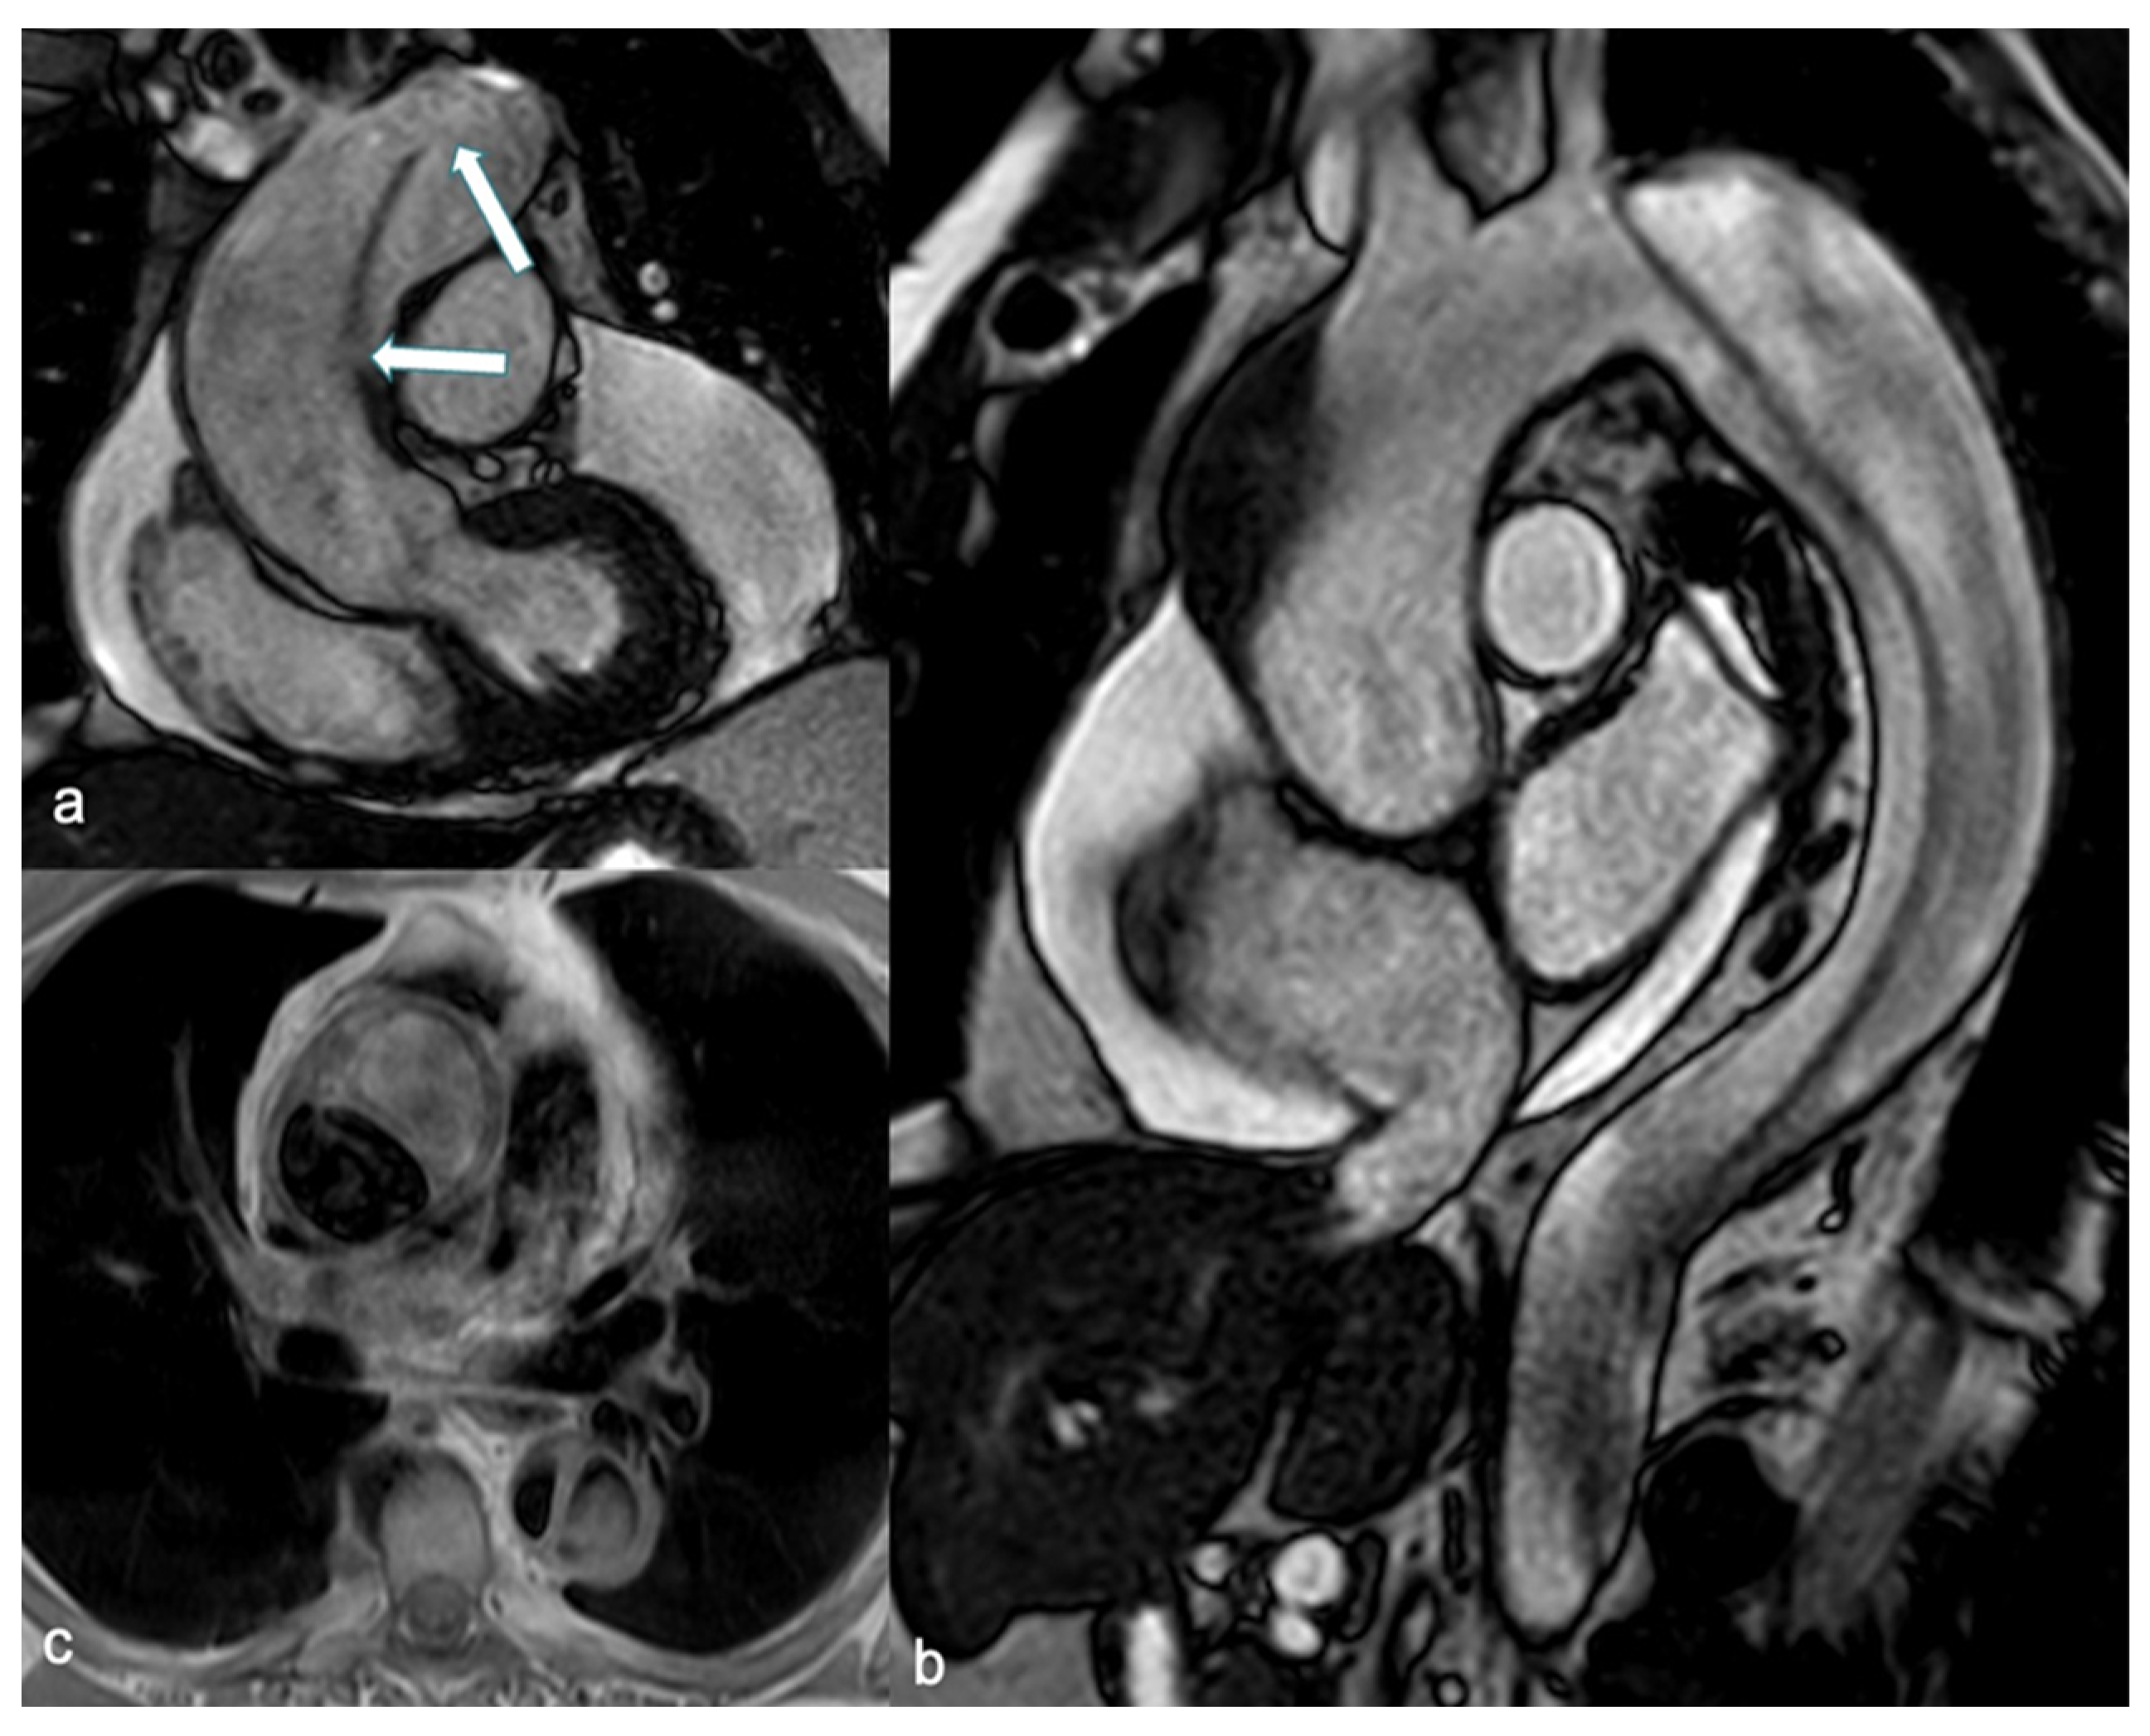

5.2. CMR Assessment

- Ordovas, K.G.; Baldassarre, L.A.; Bucciarelli-Ducci, C.; Carr, J.; Fernandes, J.L.; Ferreira, V.M.; Frank, L.; Mavrogeni, S.; Ntusi, N.; Ostenfeld, E.; et al. Cardiovascular magnetic resonance in women with cardiovascular disease: Position statement from the Society for Cardiovascular Magnetic Resonance (SCMR). J. Cardiovasc. Magn. Reson. 2021, 23, 52. [Google Scholar] [CrossRef] [PubMed]

- Wong, D.T.; Richardson, J.D.; Puri, R.; Nelson, A.J.; Bertaso, A.G.; Teo, K.S.; Worthley, M.I.; Worthley, S.G. The role of cardiac magnetic resonance imaging following acute myocardial infarction. Eur. Radiol. 2012, 22, 1757–1768. [Google Scholar] [CrossRef] [PubMed]